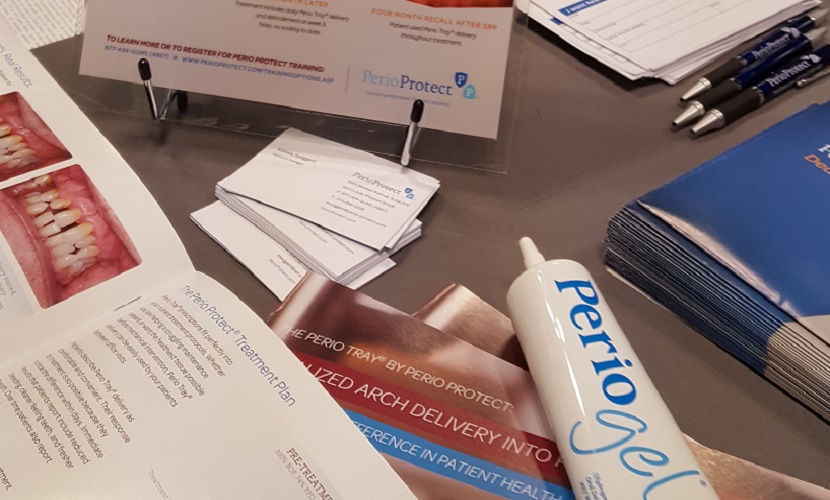

マウスピース矯正+(歯周病予防)

マウスピース矯正をしながら、ペリオジェルやなどをマウスピース内に塗布して使用します。唾液に直接さらされないため、効果的に歯周病予防ができます。